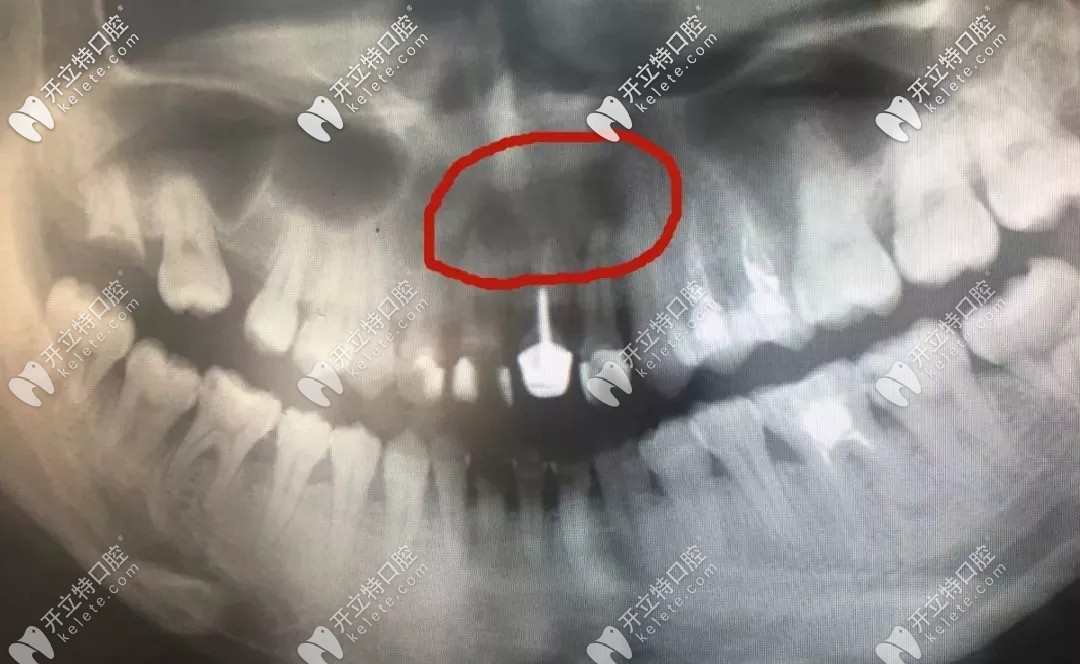

牙根尖的囊腫

▲牙根尖的囊腫

起初只是上門牙長蛀牙有兩三年,平常吃東西總是塞牙,還經(jīng)常發(fā)炎疼痛,但她一直拖著沒處理;后來導(dǎo)致齲洞越來越大,牙神經(jīng)壞死,并在牙根尖處形成慢性炎癥,時間一長,根尖的慢性炎癥就病變成了根尖囊腫,導(dǎo)致局部牙槽骨吸收,在頜骨內(nèi)形成內(nèi)含囊液的空腔。